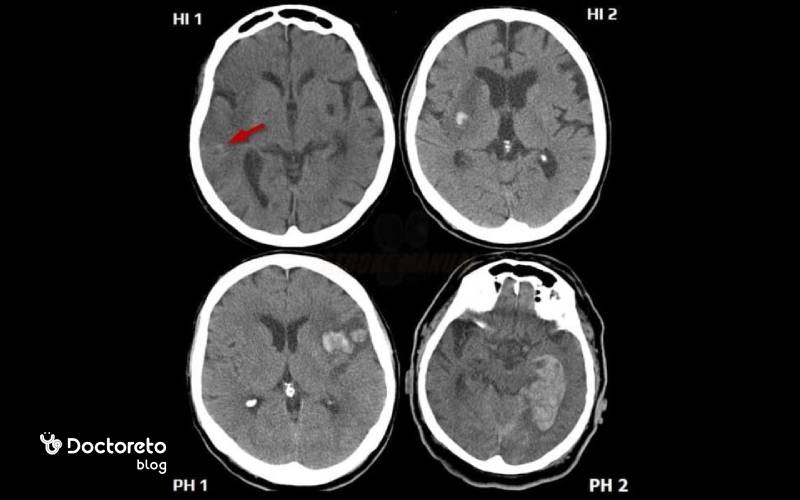

معاینه فیزیکی بیماران مبتلا به خونریزی مغزی معمولا بر اساس محل خونریزی متفاوت است. ارزیابی بیماران شامل بررسی علائم حیاتی و ارزیابی سطح هوشیاری یا GCS آنها است. معمولا ارتباط خونریزی مغزی و سطح هوشیاری به این صورت است که با افزایش شدت خونریزی، سطح GCS هم به شدت کاهش مییابد و حتی ممکن است به تدریج بیماران به کما بروند اما این رابطه در همه بیماران یکسان و قطعی نیست. پزشکان سطح هوشیاری بیماران را با نتایج به دست آمده از آزمایش MRI/CT میسنجند.

پزشک چطور تشخیص می دهد خونریزی مغزی باعث افت هوشیاری شده است؟

پزشکان میتوانند با کمک معاینات فیزیکی بیماران، بررسی مقیاسهای AVPU و همچنین تفسیر نمره مقیاس کمای گلاسکو، تشخیص دهند که آیا خونریزی مغزی باعث افت هوشیاری بیماران شده یا خیر. در صورتی که علائم حیاتی بیمار و مواردی مانند پاسخگویی به درد یا سایر محرکها، منفی باشد، به این معنی است که خونریزی مغزی باعث کاهش سطح هوشیاری شده است.